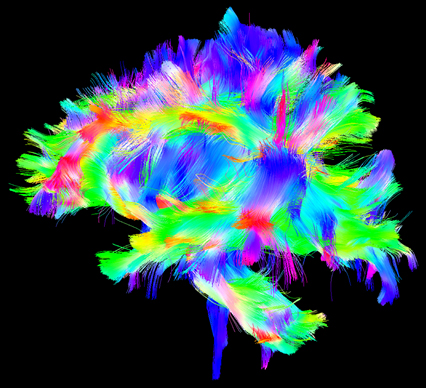

Diffusion tensor imaging technique on brain white-matter fiber tracts.